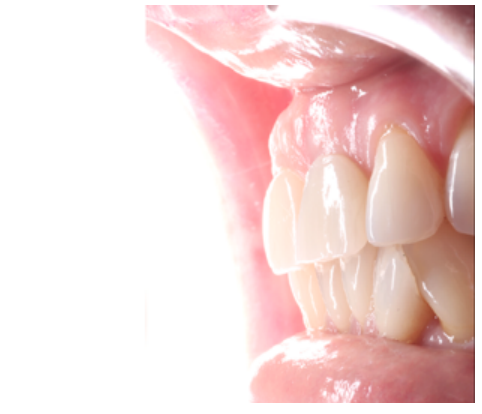

The first review of the surgical procedure was carried out 7 days later. Proper initial healing of the soft tissues and a lack of infectious or inflammatory pathology were observed (Figure 18). At 14 days, a second review was performed when the suture was removed (Figure 19). The review one month after surgery showed proper initial stability of the soft and hard tissues, as well as the absence of any signs related to the failure of the procedure (Figure 20).

At 4 months, good stability of the OII was seen as a result of the proper osseointegration process. For the soft tissues, a decrease in the volume of the interdental papilla could be seen (Figure 21). Given the absence of signs and symptoms and the proper osseointegration of the OII, the subcritical profile was modified to improve the arrangement of the gingival soft tissue and promote recovery of this papilla (Figures 22 and 23).

At 6 months, proper arrangement of the soft tissues could be seen, with their stability over time due to their handling through the provisional prosthesis (Figure 24).